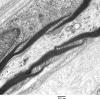

3 NORMAL MYELIN & SCHWANN CELLS

1 Myelin